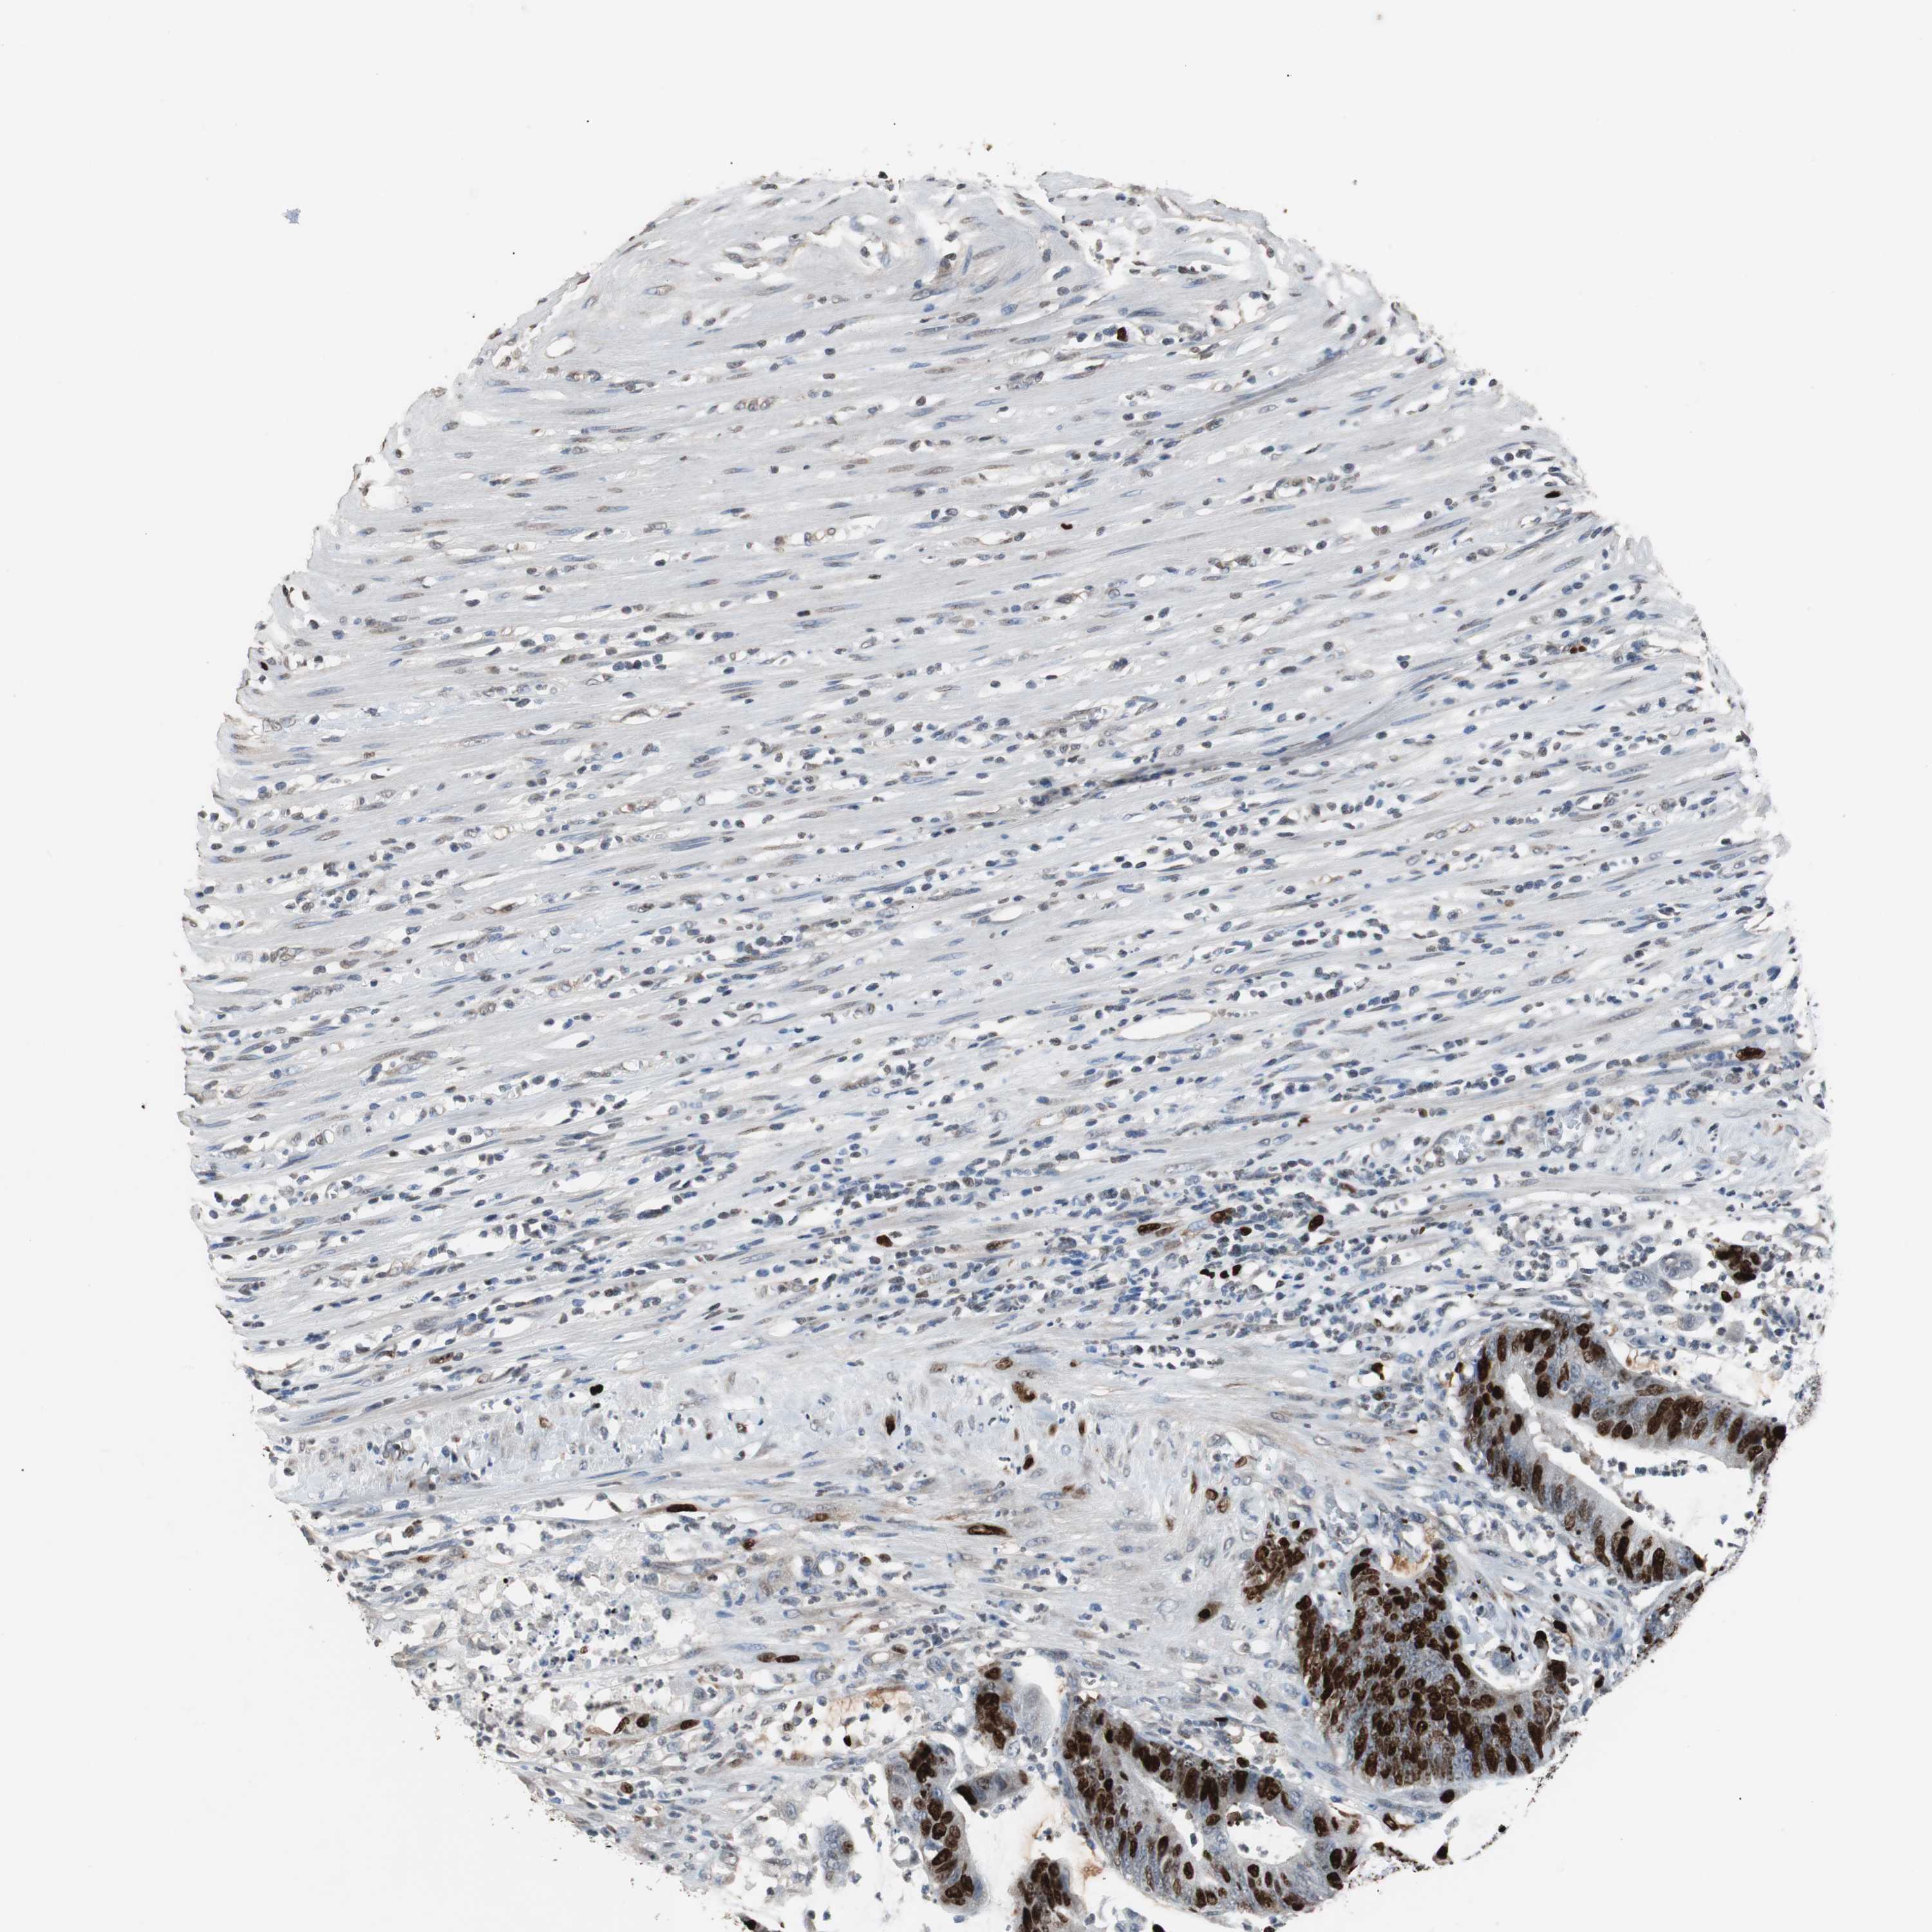

CANCER COLORECTAL CANCER Show tissue menu

Colorectal cancer

Human cancer

Colon adenocarcinoma